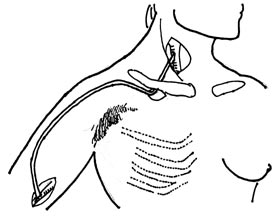

| Fig.

4 |

Schematic drawing of the anatomic

situation in a carotid-brachial bypass graft. The 6

mm ring supported Dacron graft is placed subcutaneously

avoiding areas of previous irradiation and scarring. |